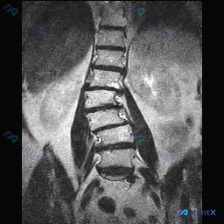

整理到一份腰椎MRI-T2冠状位的影像资料,第一眼就能看到明确的脊柱侧弯——腰椎呈C型向左侧凸。 但仔细看还有几个点: 1. 侧弯凸侧(右侧)椎体边缘有不同程度骨赘形成 2. 双侧小关节增生明显,关节周围有高信号 3. 椎间隙左右不对称,凹侧(左侧)椎间孔空间看起来受压缩 4. 目前层面没看到明确的...